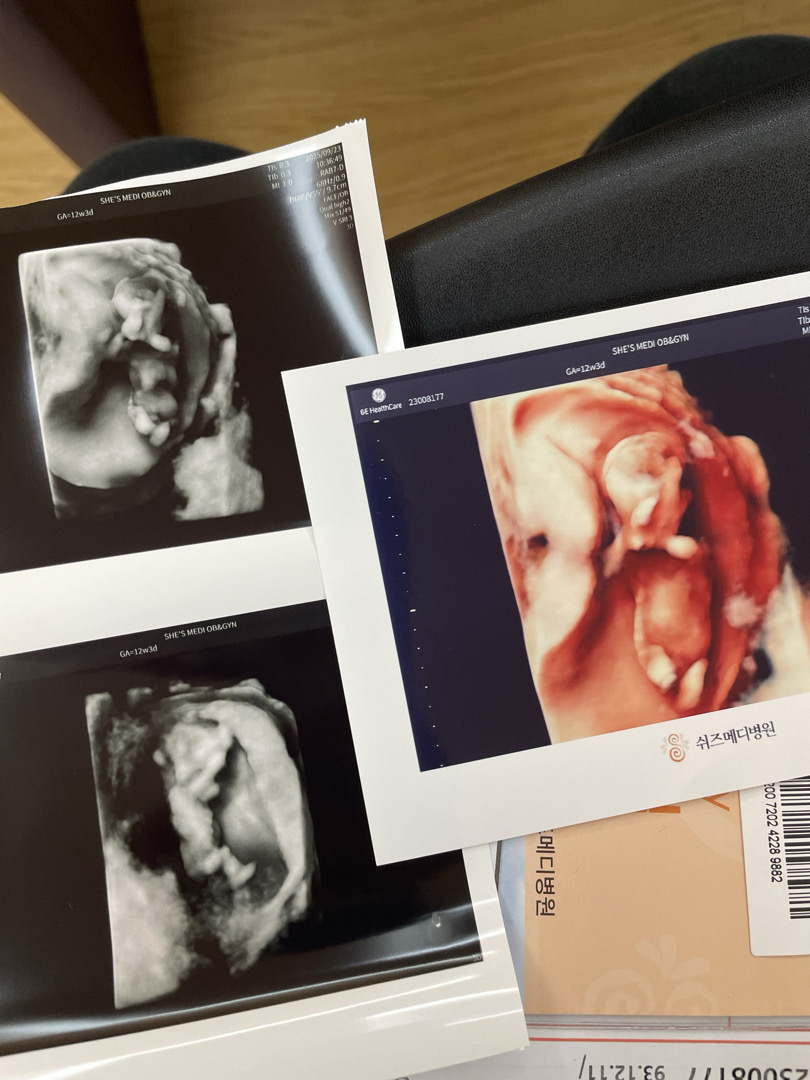

12주 1차기형아검사까지 완료!

무사히 검진 잘 봤네요 ㅠㅠ 이사진 봐서는 성별을 알기는 힘들겠죠?! 첫째가 아들이라그런가 더욱 더 성별이 궁금하구 긴장됩니닷,,